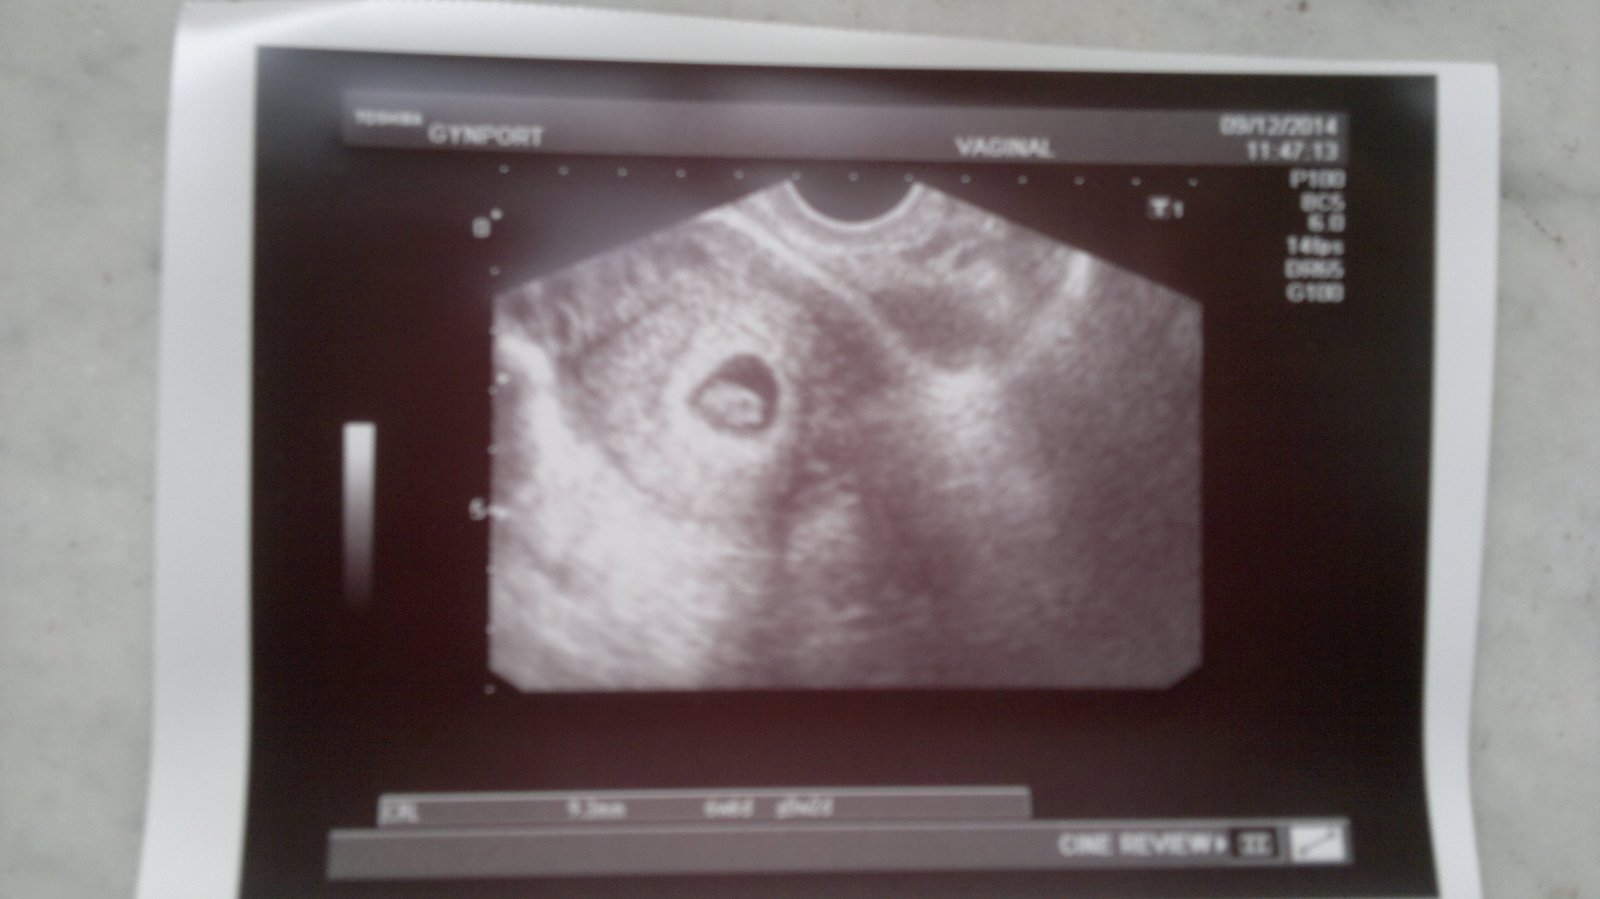

kata1988 (26let, MA 1/2014, Nosifol).......................................................................................33 DC // 9.12.

Ahojky, tak musím trochu upravit své včerejší hlášení 😀 dnes jsem delala test a vykoukly na mě //. Do tabulky to zatim davat nebudu dokud to nebudu mít potvrzené od doktora😉